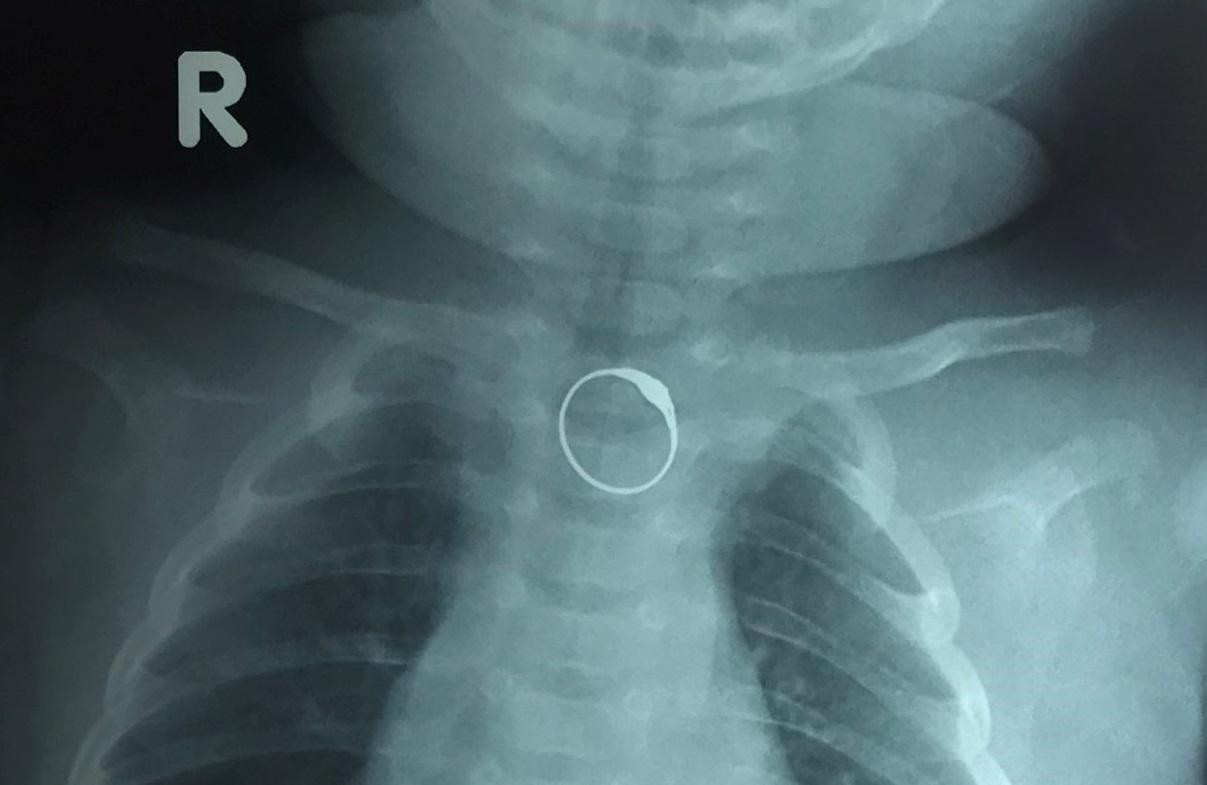

| Hình ảnh X-quang phát hiện dị vật là chiếc nhẫn đang bị kẹt ở thực quản của bệnh nhi |

Sau khi thăm khám, các bác sĩ đã tiến hành chụp X-quang kiểm tra thì phát hiện hình ảnh cản quang của dị vật dạng kim loại giống chiếc nhẫn nằm trong thực quản đoạn thực quản ngực của bệnh nhi. Chiếc nhẫn có hoa văn được trang trí tạo thành những góc cạnh nhọn và sắc nguy cơ gây tổn thương thực quản của trẻ.